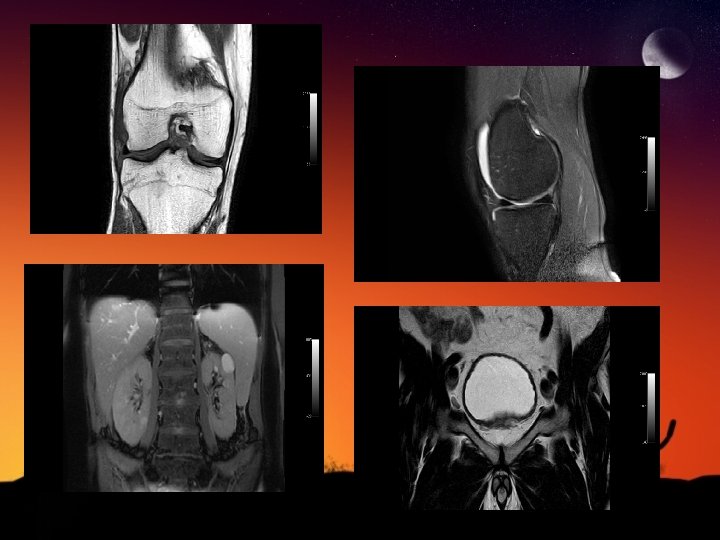

Les incontournables (2) 1/ La hernie discale cervicale 2/ L’ostéonécrose de hanche 3/ La pathologie ménisco-ligamentaire du genou 4/ La maladie de Morton 5/ Les voies biliaires: bili-IRM 6/ L’hémochromatose

Les incontournables (2) 3/ La pathologie ménisco-ligamentaire du genou

Les incontournables (3) cancer de la prostate

IRM RÉNALE et SURRÉNALIENNE ◊ Bilan d’un kyste atypique au scanner (classification de Bosniak) ◊ Angiomyolipome pauvre en graisse ◊ Caractérisation d’une masse surrénalienne